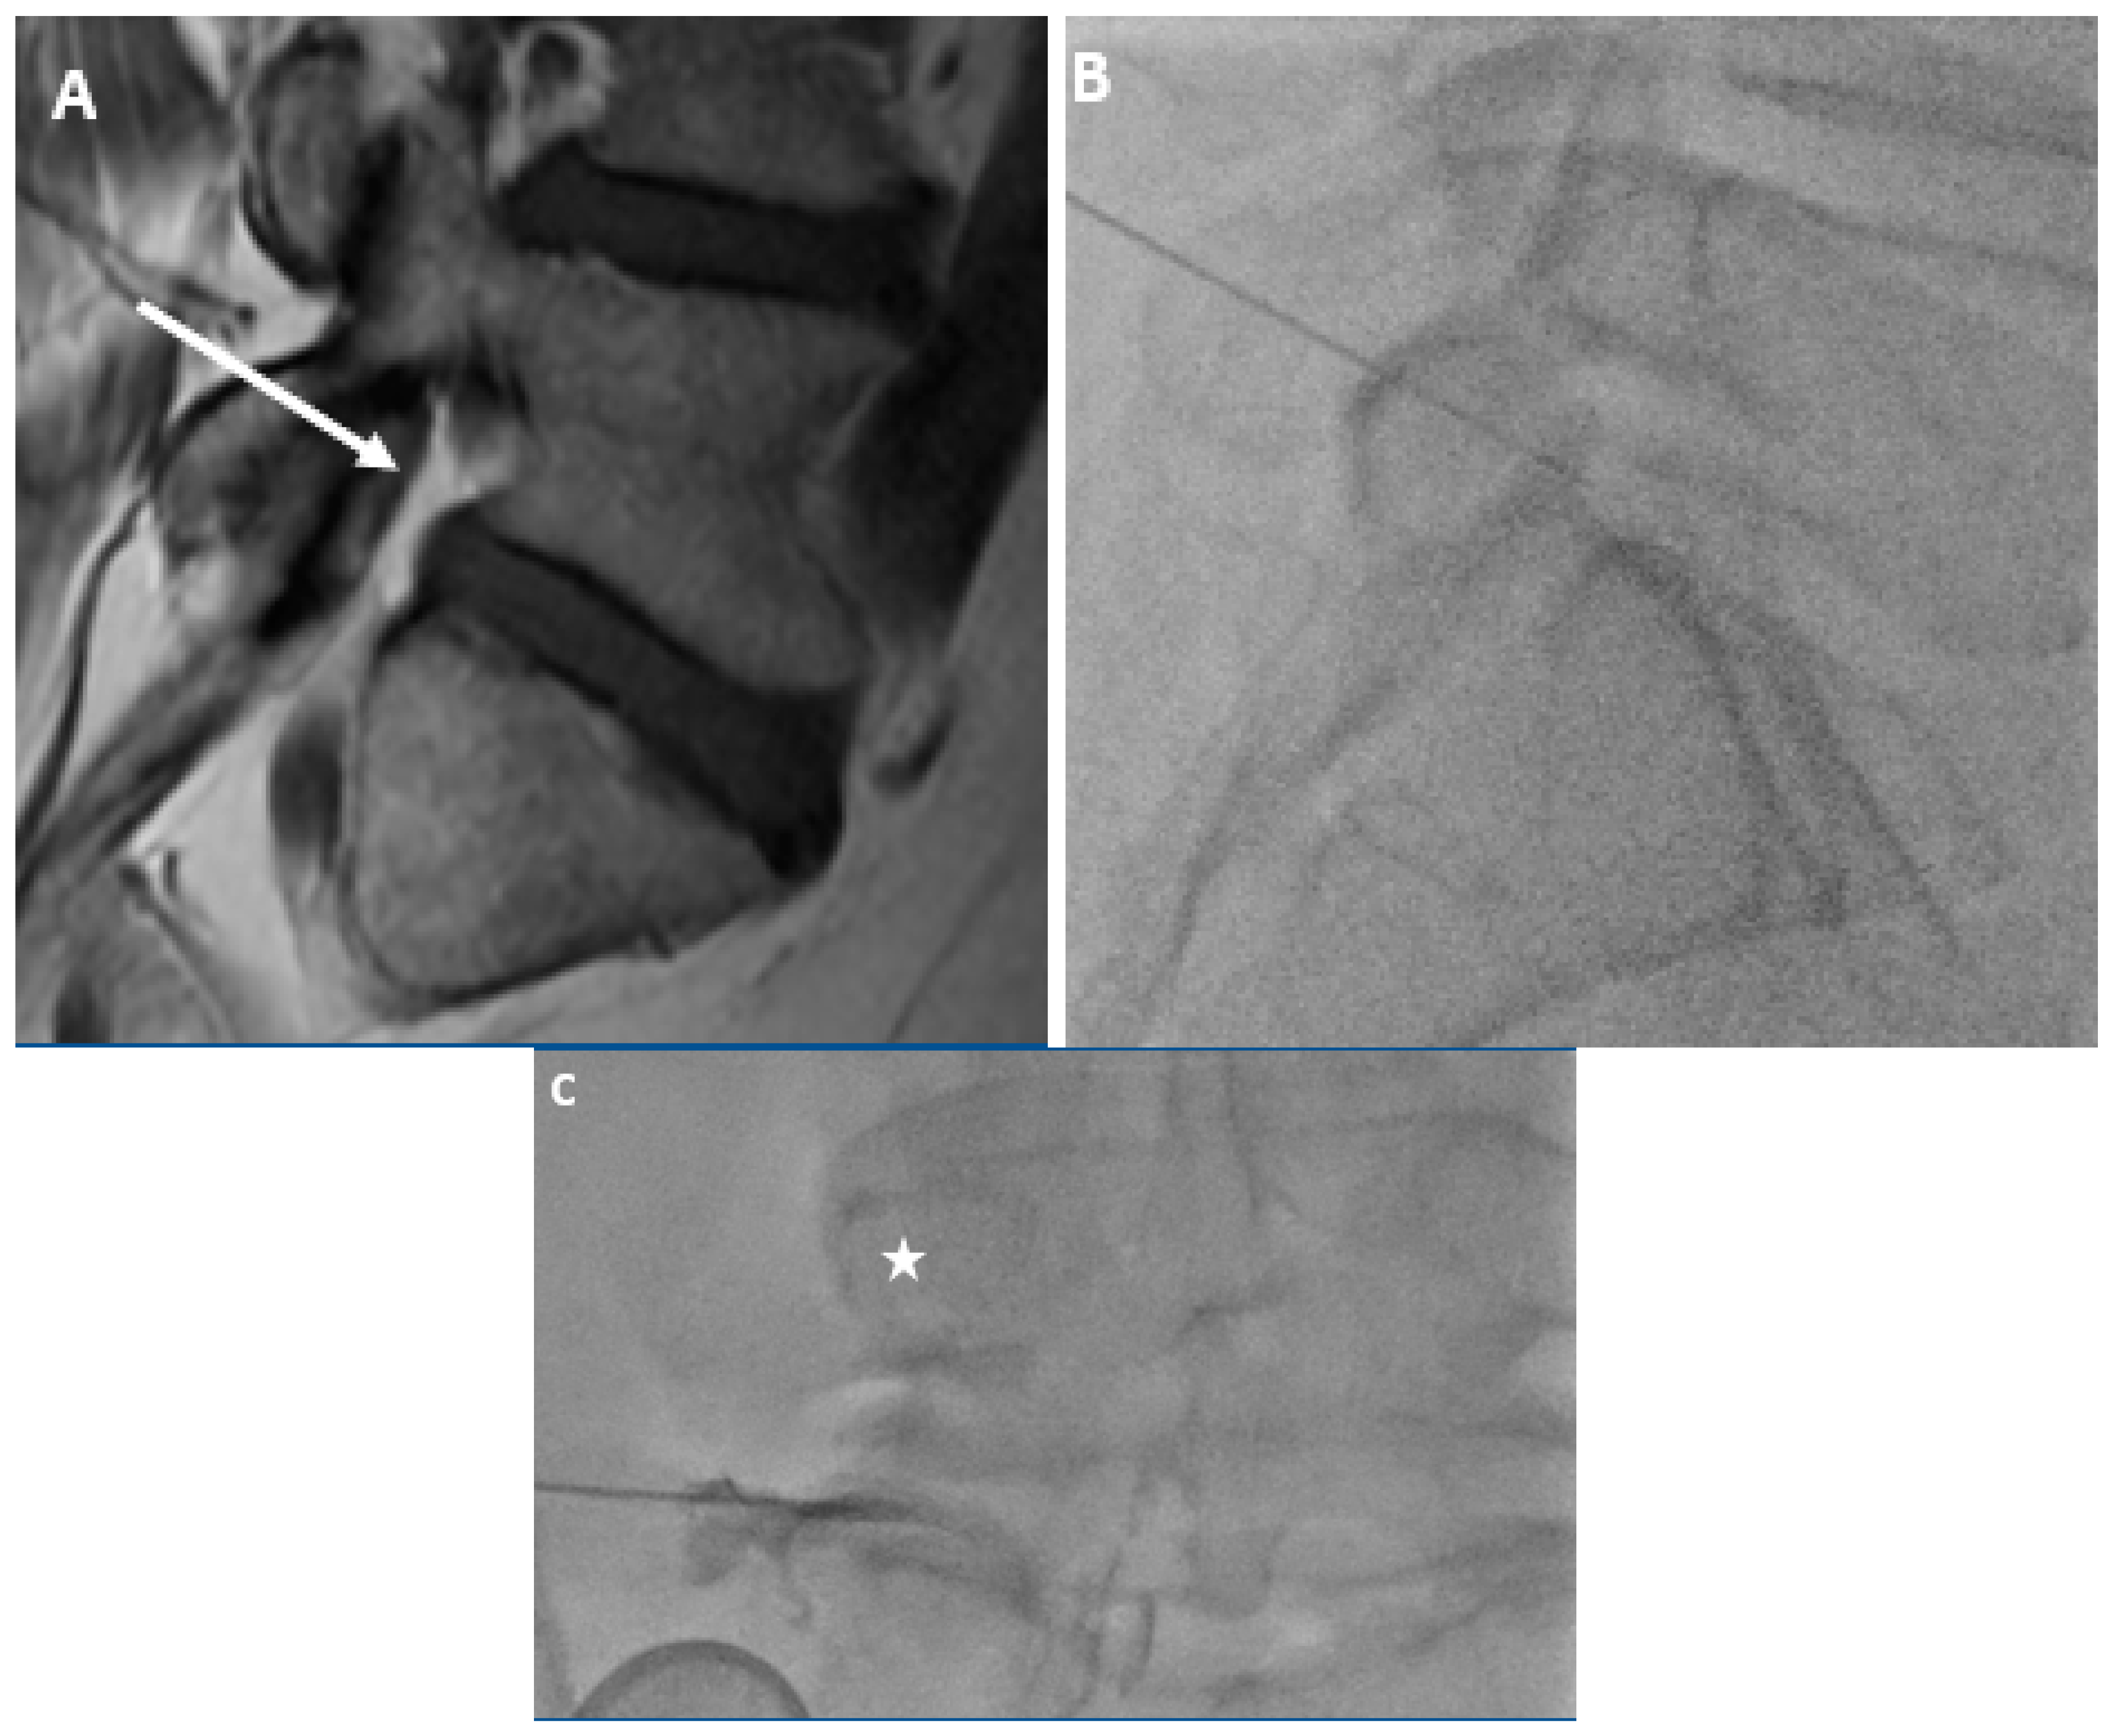

The semi-quantitative method for determining the amount of fat in both the antero-superior and the postero-inferior aspects of the neural foramina was based on the diameter of a 22-gauge needle, which is ~0.7 mm. With this as the standard, the reviewers were instructed to grade the fat as “None” if there was less than 0.8 mm of distance in any direction between nerve and bone/disc material, “Minimal” if there was 0.8 mm to 2.5 mm of distance, and “Substantial” if there was more than 2.5 mm of distance. These numbers reflect, in essence, a space too small to accommodate a 22-gauge needle, a space that is 1–3 times the size of a 22-gauge needle, or a space that can accommodate more than 3 times the diameter of a 22-gauge needle (Figure 1).

Figure 1.

Representative sagittal T1w MR images at the level of the L5-S1 neural foramen demonstrating the foraminal fat grading system. (A) demonstrates “No fat” in either the antero-superior or postero-inferior portions of the foramen. (B) demonstrates “Minimal fat” in the antero-superior foramen and “Substantial fat” in the postero-inferior foramen. (C) demonstrates “No fat” in the antero-superior foramen and “Minimal fat” in the postero-inferior foramen. (D) demonstrates “Substantial fat” in both the antero-superior and postero-inferior foramen.